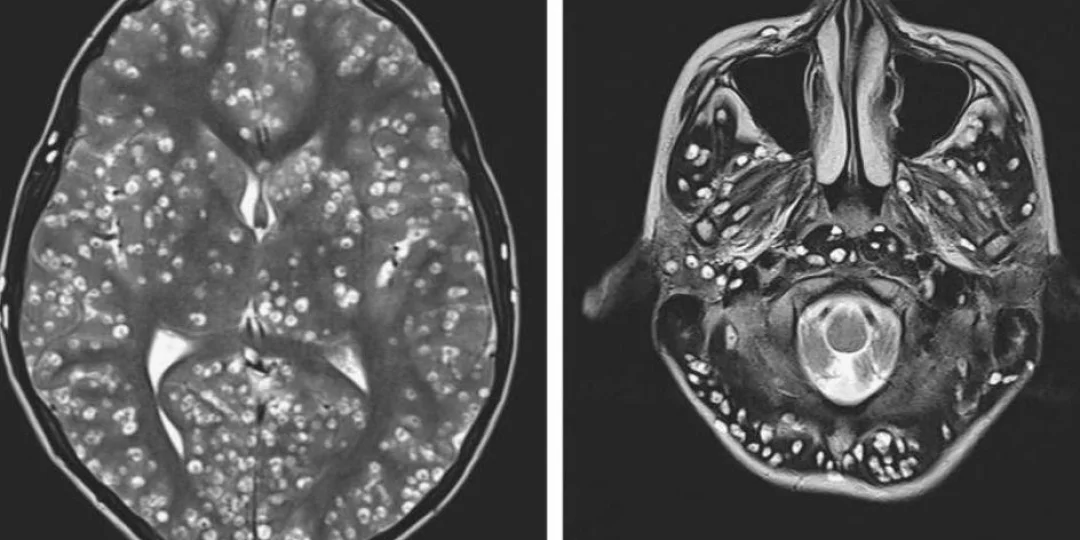

El joven, de quien se preserva su identidad, fue sometido a una resonancia magnética donde se descubrió la gran cantidad de huevos de parásitos en la corteza cerebral, en el tronco cerebral (incluido el cerebelo) y por encima de la médula espinal.

El diagnóstico fue determinante: neurocisticercosis. Se trata de una enfermedad de origen parasitario que es causada cuando un individuo ingiere huevos de Tenia. Las larvas se arrastran fuera de los huevos hacia los tejidos musculares y cerebrales, donde forman quistes, informó CNN en español. Además los médicos descubrieron quistes en el ojo derecho y el testículo derecho del paciente.